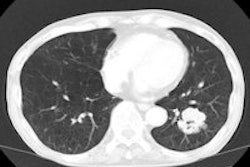

Isodose lines for the case of seeds loaded in the pair of acrylic inserts. Blue, green, and red contours represent film dosimetry measurements, TG-43 and ICF-corrected TG-43 dose distributions, respectively.Dose distributions generated using the ICF formalism showed better agreement with film measurements than the TG-43 distributions did. For seeds inserted in acrylic, for example, the isodose lines for film and ICF calculations bent in toward the Teflon rod (due to its higher attenuation compared with water) and bulged out from the polypropylene rod (which attenuates less than water). ICF-calculated isodose lines matched the measurements well, while the TG-43 dose distribution was unaffected by the heterogeneities. The GI passing rate for 2%/2 mm was 22.0% for TG-43, improving to 75.8% for ICF dose distributions.